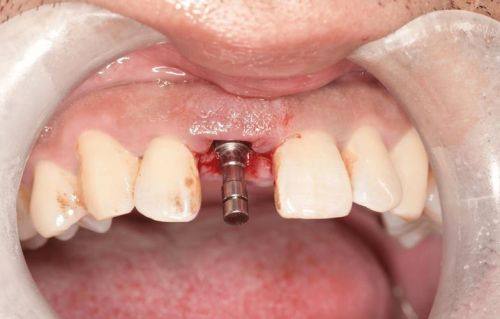

特别多人忽略了一个细节:诊疗效率的提升也能降低成本。中诺口腔引入的智能化导航种植技术,将传统种牙中依赖医生经验的环节转化为数据化操作,不仅缩短了手术时间,还减少了反复调整导致的耗材损耗。例如,某智能化导板技术可将单颗种植牙的操作时间压缩30%,术后改善周期同步缩短,间接降低了患者的复诊成本和时间投入。

此外,技术升级带来的成功概率提升,避免了因种植失败导致的二次治疗费用。传统模式中,患者可能因医生经验不足或设备落后承担额外风险,而中诺口腔通过标准化流程和新型设备,将种植牙的成功概率维持在较优质水平,从长远看反而更省钱。中诺口腔应用的即刻负重技术(如“立得用”),实现“当天种牙当天用”,将传统种植3 - 6个月的愈合周期压缩至24小时内。